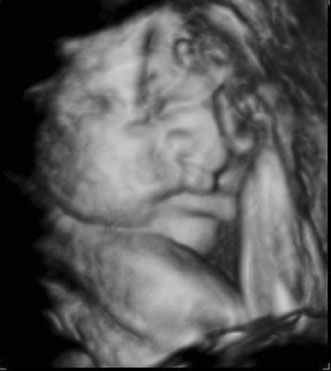

Diagnostic ultrasound is widely used in the assessment of pregnancy and the fetus. Although clinical benefits of routine ultrasonography during pregnancy have not been established, approximately 70% of pregnancies in the United States undergo ultrasound evaluation.30 Because most instruments used in diagnostic ultrasonography produce energies no greater than 10 to 20 mW cm2 (safety defined as less than 100 mW cm2), ultrasound is considered generally safe. No harmful biologic effects on instrument operators, pregnant women, fetuses, or other patients have been found. Infants exposed in utero have shown no significant differences in birth weight or length, childhood growth, cognitive function, acoustic or visual ability, or rates of neurologic deficits (see Fig. 6).

Fig. 6. A: First-trimester twin intrauterine gestations. Ultrasound examination of the pregnant uterus (arrowheads) shows the “owl eyes” characteristic of early twin pregnancies. B: Maternal urinary bladder. (Courtesy of Alfred B. Kurtz, MD)